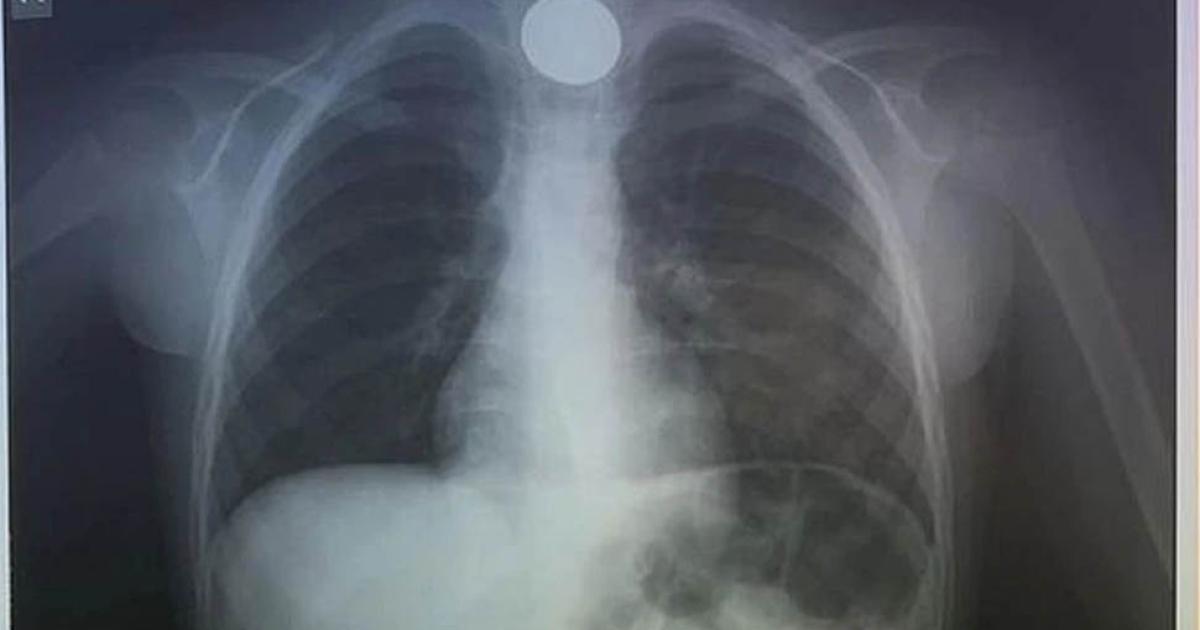

Η πρώτη κίνηση των γιατρών, ήταν να του κάνουν ακτινογραφία, για να δουν το σημείο που είχε σταθεί το νόμισμα.